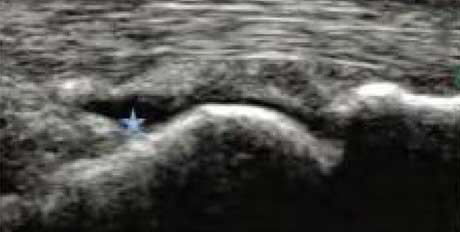

1、动态观察滑膜血流信号,早期监测RA活动

肌骨超声血流成像可清晰反映滑膜的血流情况,观测滑膜周边及内部异常血流信号的增多、血管翳增生程度,以及呈现出点状、星点状或枝状的不同形态,做到在RA的早期发现异常图像变化。通过对图像中血流信号的多少及区域范围进行评分,以此来辅助判断RA的活动程度。

Ⅰ级血流

滑膜内异常血流信号:少量点状血流信号

Ⅱ级血流

滑膜内异常血流信号:较多点状,短线状血流信号

Ⅲ级血流

滑膜内异常血流信号:丰富的网状及树状血流信号